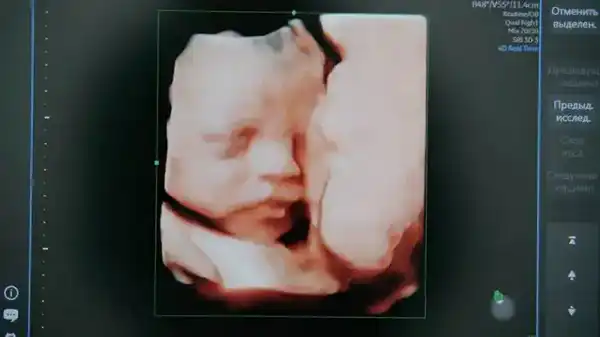

Проект основан на системе искусственного интеллекта, предназначенной для анализа УЗИ-снимков, которая была разработана на платформе Yandex Cloud с участием Центра технологий для общества. Она будет использоваться для обработки изображений, полученных в ходе первого скрининга, проводимого на 11—14 неделе беременности.

Специалисты будут использовать искусственный интеллект для анализа результатов УЗИ беременных, что позволит выявлять мельчайшие детали, которые могут быть упущены человеком. Вся информация будет обрабатываться без использования персональных данных пациентов, а облачные технологии Yandex Cloud обеспечат безопасность хранения и обработки данных.